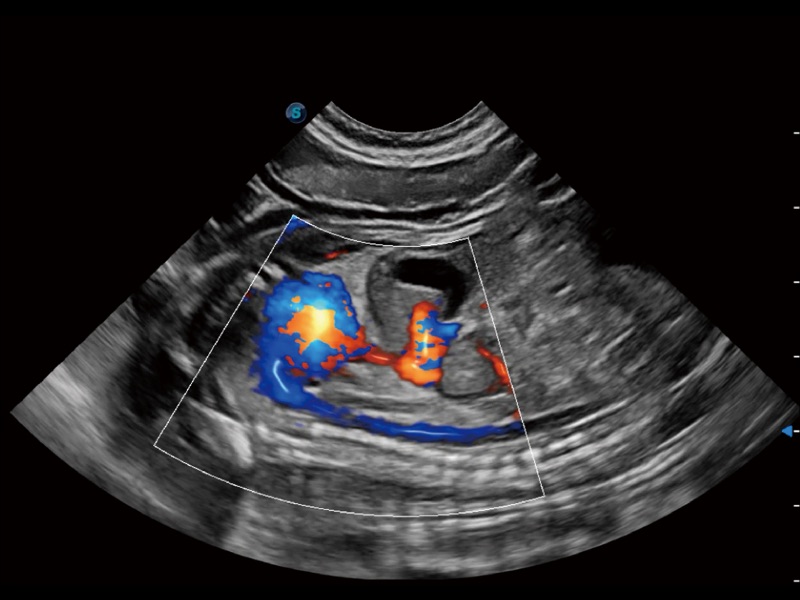

(犬)四腔心

(犬)胎儿主动脉弓立体血流